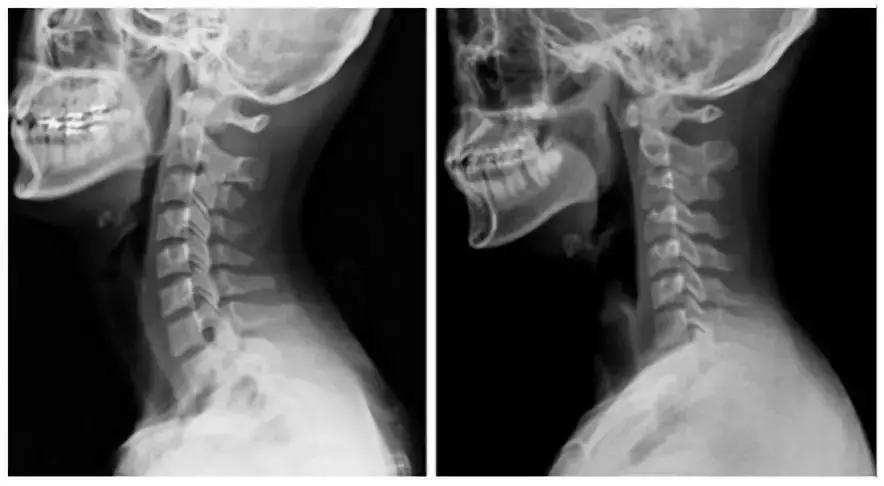

颈椎病已成为现代人的常见病。据统计,我国颈椎病的发病率高达17.3%,且呈现年轻化趋势。长期伏案工作、使用电子设备等不良姿势,都可能导致颈椎受损。如果不及时干预,可能会引发头痛、眩晕、肩背疼痛等症状,严重影响生活质量。